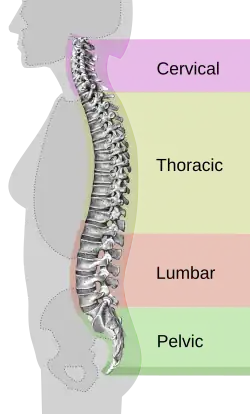

Anatomy of the spine

The spine is one of the main components of the central nervous system (CNS). This structure's function is to provide the body with support and to protect the spinal cord. The spinal cord serves 3 main functions for the body. It provides sensation, autonomic and motor control for all bodily functions and parts. The spinal cord is the most complex yet organized part of the CNS. The entire spinal structure may be divided into 4 sections that create an overall S-shaped curve. These sections include the cervical, thoracic, lumbar, and sacral regions. Intervertebral discs stacked on top of one another make up the structure of the overall spine. These discs are separate and cushioned in between them, and with age, these discs become brittle and flat. Sensory stimulation is recognized and processed through the spinal cord, these include pain and temperature, touch, and proprioception. Our body's entire neural network sends any of this sensory information to the spinal cord to process. In order to stabilize spinal movement, there are many ligaments throughout the spine to hold the vertebrae and intervertebral discs together. These elements all working together allow for spinal movement and overall bodily stability and support.[2]